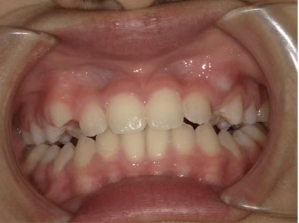

治療前① 小1:6y8m 初診

| はじめのご相談 | 乳歯列期に受け口だったため他院で診てもらったが矯正治療のコンセプトがよくわからないので教えてほしい |

| カウンセリング・診断結果 | 前歯の生え変わり時期に来院されました。(写真①) 乳歯列期に受け口の既往があり切端咬合になりそうなため、受け口に対する矯正治療の考え方と対処法、当院のコンセプトを説明したところ治療を希望されたので診断を行いました。 診断の結果、上顎骨に対し下顎骨が長く、骨格的な構造も下顎突出型反対咬合(下顎骨が適切な位置よりも前に出ているタイプの受け口)と分かりました。 顔立ちは、中顔面が引っ込んだように見えるコンケーブに移行中です。 機能的な問題として低位舌があるため受け口の悪化が考えられることも説明し、以下の治療を提案しました。 |